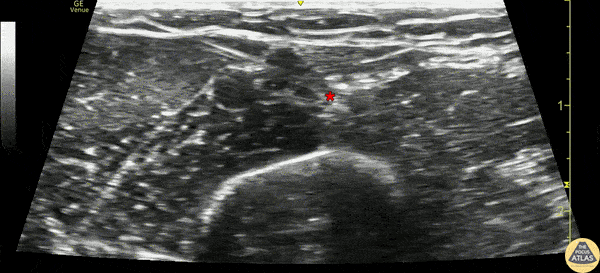

20s F presented with large complex laceration to the distal forearm after an assault. Ultrasound radial and median nerve blocks were performed at the elbow to facilitate washout and closure. This clip illustrates the median nerve block, where the needle is entering from the lateral/radial aspect of the upper arm, and anesthetic can be seen adjacent to the median nerve (*). Dr. Gabe Siegel Denver Health Residency in Emergency Medicine